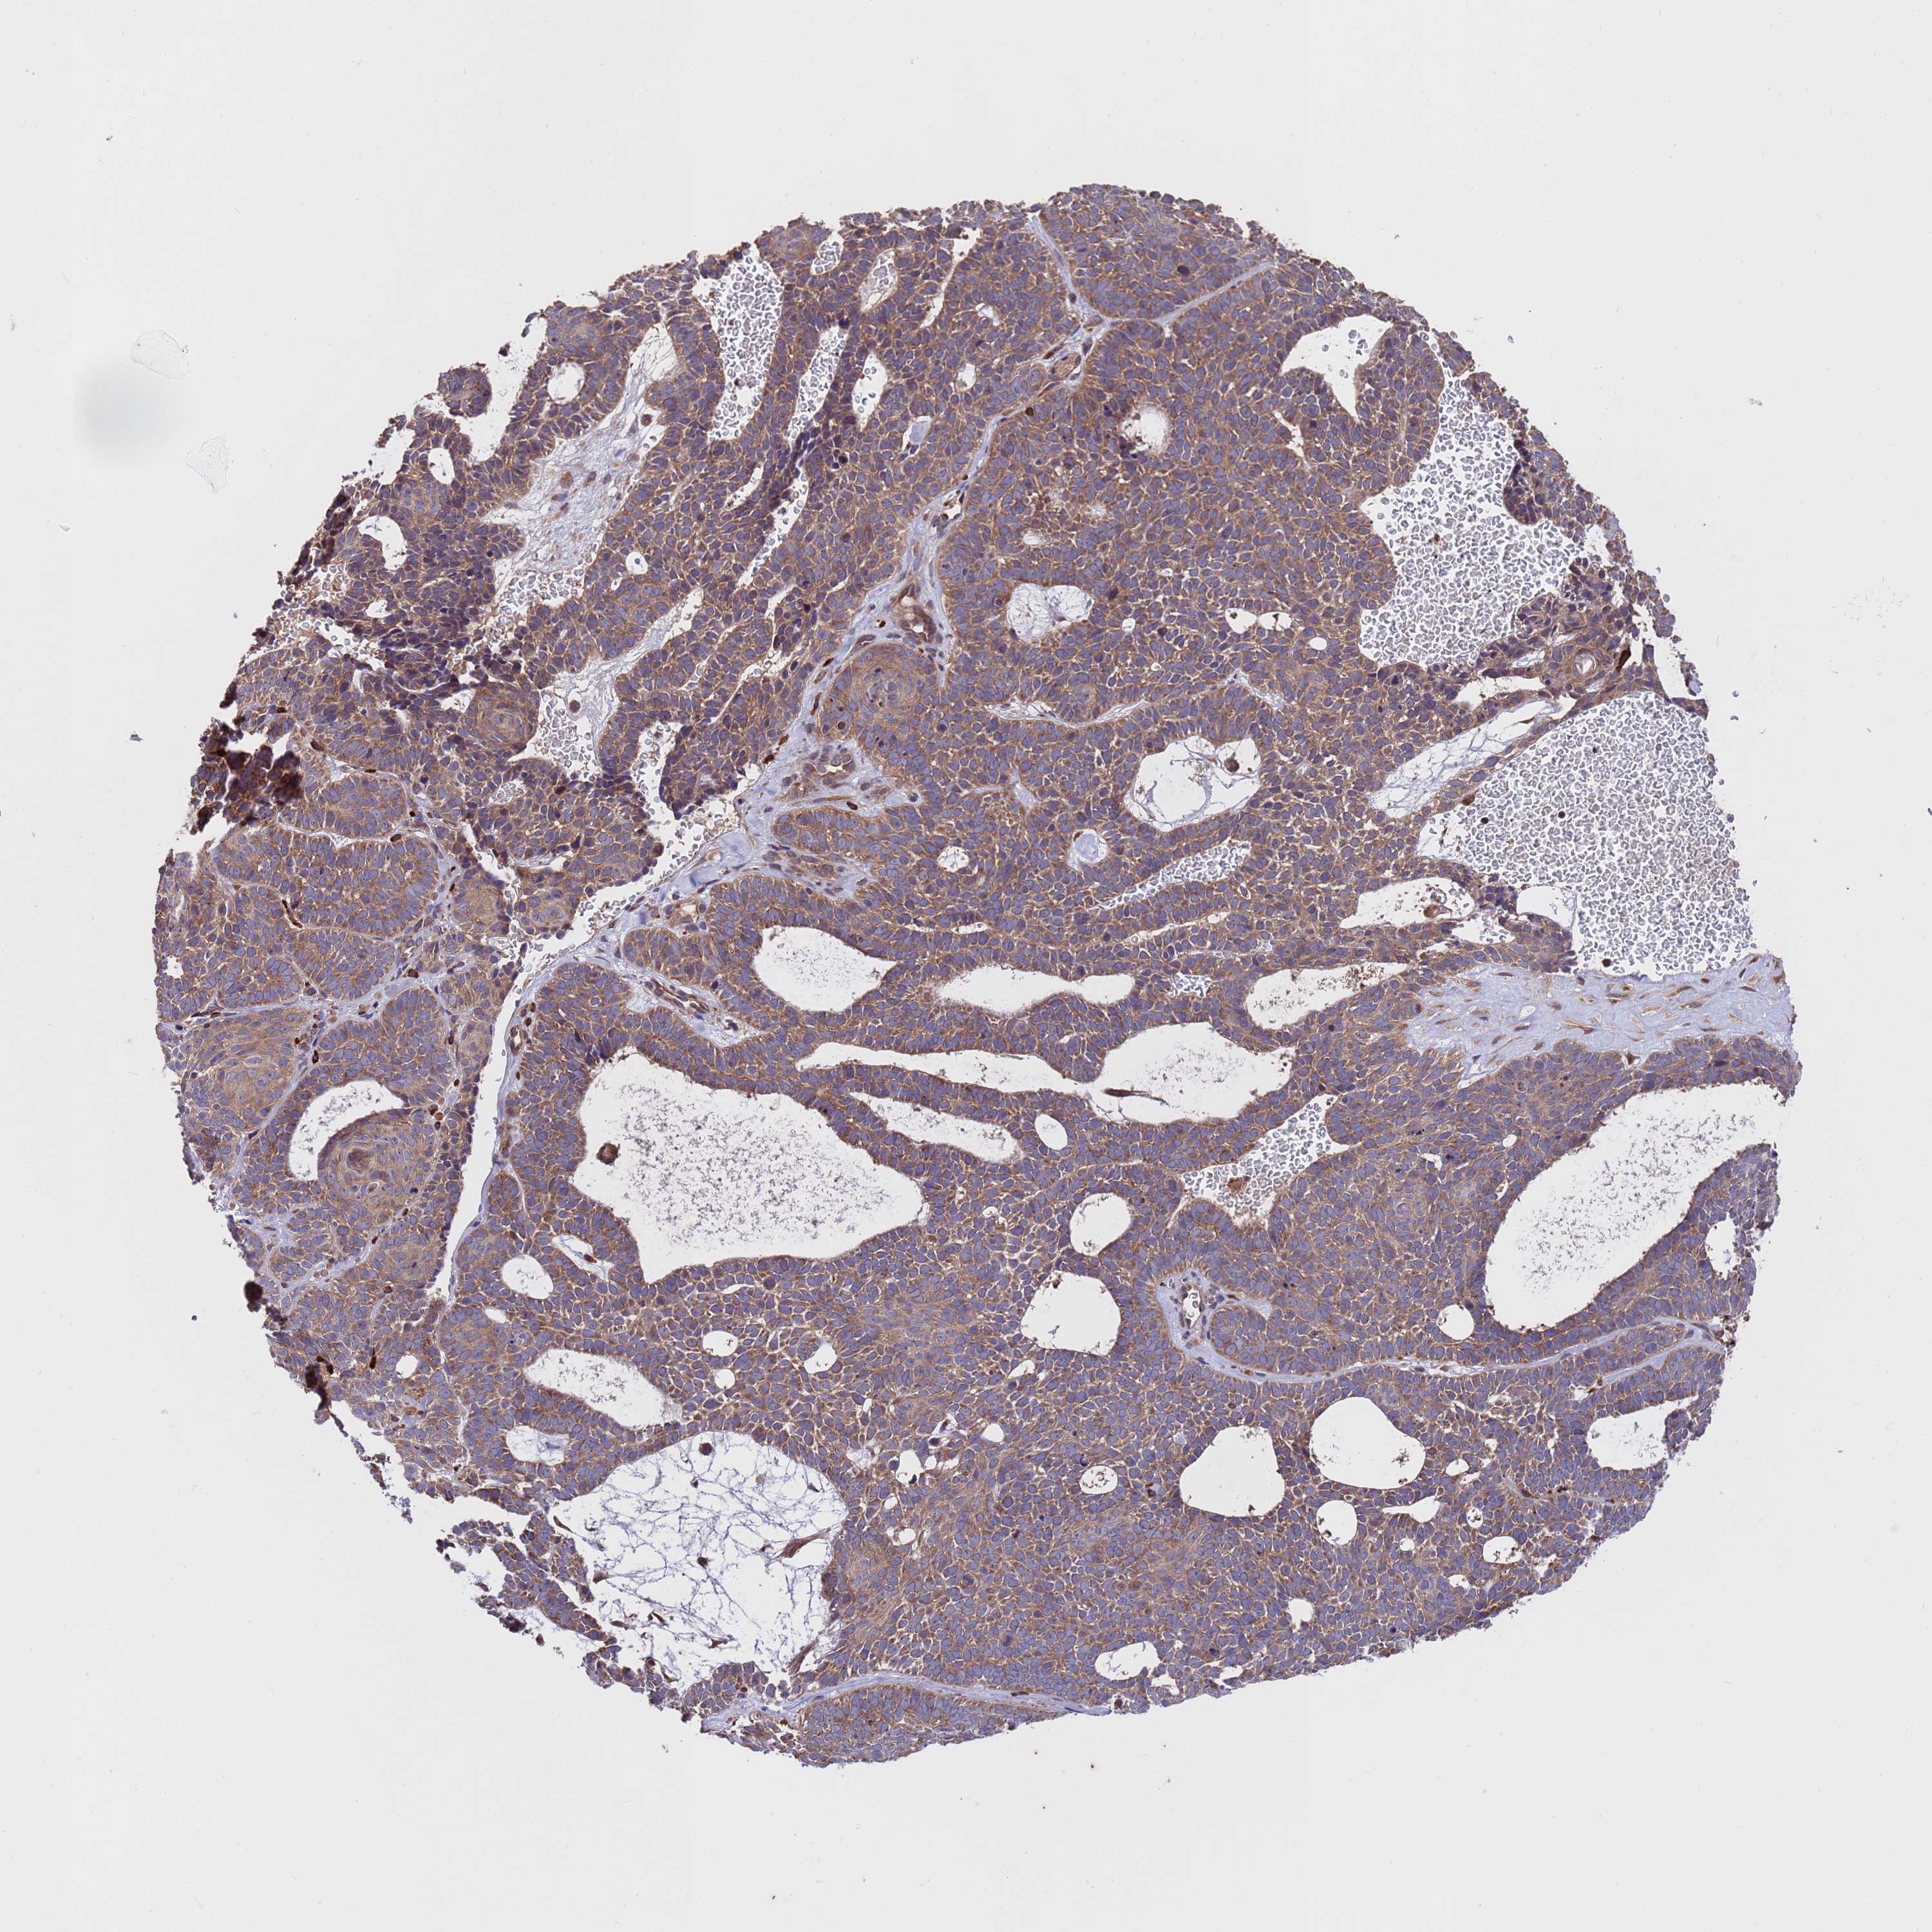

SKIN CANCER - Protein expressioni

A mouse-over function shows sample information and annotation data. Click on an image to view it in a full screen mode. Samples can be filtered based on level of antibody staining by selecting one or several of the following categories: high, medium, low and not detected. The assay and annotation is described here.

Antibody stainingi

Antibody staining in the annotated cell types in the current human tissue is reported as not detected, low, medium, or high, based on conventional immunohistochemistry profiling in selected tissues. This score is based on the combination of the staining intensity and fraction of stained cells.

Each image is clickable and will lead to virtual microscopy that enables deeper exploration of all samples and also displays staining intensity scores, fraction scores and subcellular localization as well as patient and tissue information for each sample.

Antibody HPA046265

Staining

High

Medium

Low

Not detected

Intensity

Strong

Moderate

Weak

Negative

Quantity

>75%

75%-25%

<25%

None

Location

Nuclear

Cytoplasmic/membranous

Cytoplasmic/membranous,nuclear

Squamous cell carcinoma, NOS